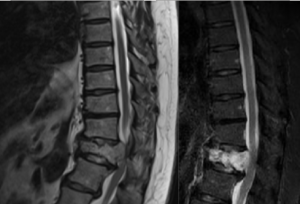

なくなった骨の名前は胸椎12番。T12って表現するそうですよ。

左の画像が分かりやすいかもしれません。背骨からはみ出てるモノが、神経を押しつぶしてますでしょ?正確にいうと、一部を押しつぶしかけてる状態です。

脊髄ですからね...... 高さにもよりますが、場所によっては腕から下が完全マヒを起こします。

骨が折れてるだけでも手術が必要なんですが、この血管腫を取らないと脊髄が死に、身体は確実にマヒします。